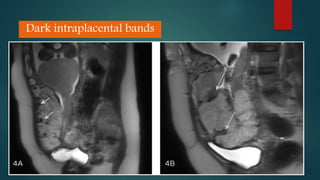

Ultrasound and MRI are used to diagnose placenta accreta, which occurs when the placenta invades the uterine wall due to prior uterine surgery or other risk factors. On ultrasound, signs include low placental implantation, lakes or indentations in the placenta, thinning of the myometrium, disruption of the uterine serosa, and abnormal blood flow on Doppler. MRI may show uterine bulging, a heterogeneous placenta, thinning and interruptions of the myometrium, obliteration of tissue planes, and dark bands within the placenta. These imaging findings help identify placenta accreta and guide management of delivery.